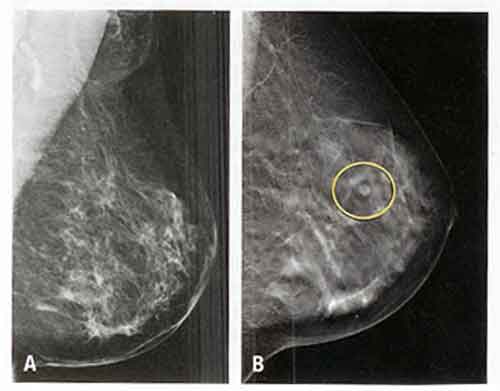

Mammografia: in grado di dimezzare mortalità per cancro al seno

Vincere il cancro del seno e’ una questione di tempo: al Sud Italia, dove viene diagnosticato mediamente piu’ tardi, il rischio di morire per questa neoplasia e’ del 50% piu’ alto rispetto al Centro-Nord. La differenza fondamentale e’ l’accesso o meno alla mammografia che, da sola, puo’ ridurre del 45% la mortalita’.

Quindi non piu’ la mammografia ogni 2 anni a tutte le donne ma una personalizzazione dei controlli sulla base del rischio individuale di ciascuna”. Secondo i risultati del progetto IMPATTO, promosso dall’Osservatorio Nazionale Screening, a partire dal 2007 tutte le regioni hanno attivato un programma di screening mammografico ma, attualmente, l’estensione effettiva e’ solo del 69,2%, con grandi differenze tra le aree geografiche. Inoltre, il tasso di partecipazione alla mammografia e’ in media del 55% (solo una donna su 2 accetta l’invito a sottoporsi all’esame), con un divario tra Centro-Nord e Sud dove i livelli di adesione sono al 40%.